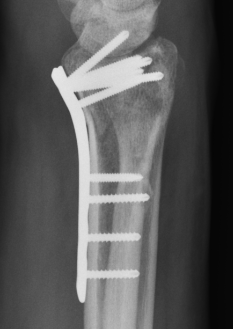

Dorsal distraction plating

Indication

Internal radiocarpal distraction

- unreconstructable distal radius fractures

- early weight bearing in poly trauma patients

- osteoporotic bone

Advantage - no pin site infection from external fixation

Disadvantage - need to remove plate at 3 - 4 months once fracture united

Technique

AO surgery foundation extended dorsal approach wrist

AO surgery foundation dorsal distraction plate

Arthrex dorsal spanning plate 2 incision video

Extended dorsal approach

- protect sensory radial nerve

- open 3rd extensor compartment / retract EPL radially

- mobilized 4th extensor compartment / retract EDC ulnarly

- bare area of radius proximally between EDC and ECRB / ECRL

Fixation to 2nd or 3rd metacarpal first

- 2nd metacarpal: under 2nd extensor compartment

- 3rd metacarpal: under 4th extensor compartment

- reduce / distract joint

- +/- additional radius fixation

Results

- systematic review of dorsal distraction plating

- 50% of wrist flexion extension compared to contralateral limb

- grip strength 80%